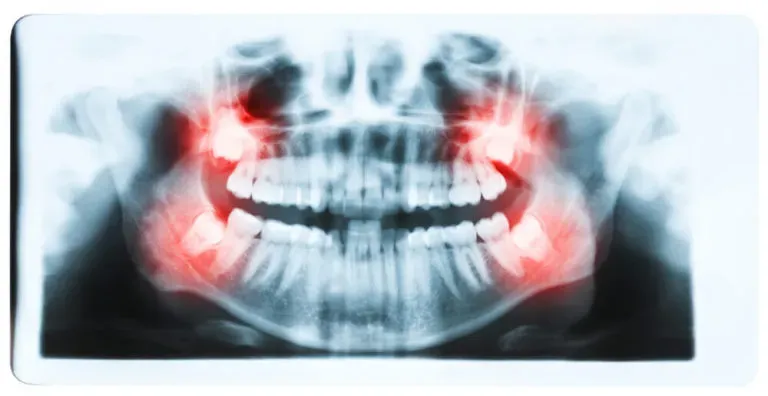

Zęby trzonowe są szczególnie narażone na różne problemy zdrowotne, które mogą wpływać na ich funkcjonowanie oraz ogólny stan jamy ustnej. Najczęściej występującymi problemami są próchnica oraz choroby dziąseł, które mogą prowadzić do poważnych komplikacji, jeśli nie zostaną odpowiednio leczone. Problemy te mogą być wynikiem niewłaściwej higieny jamy ustnej, diety bogatej w cukry, a także naturalnego procesu starzenia się organizmu. Warto być świadomym tych zagrożeń, aby móc skutecznie im przeciwdziałać.

Próchnica zębów trzonowych rozwija się, gdy bakterie w jamie ustnej produkują kwasy, które niszczą szkliwo i zębinę. Z kolei zapalenie dziąseł, znane również jako choroba przyzębia, może prowadzić do krwawienia, obrzęku oraz bólu. Jeśli nie zostaną podjęte odpowiednie kroki, te problemy mogą prowadzić do utraty zębów i innych poważnych schorzeń. Dlatego ważne jest, aby regularnie kontrolować stan zębów trzonowych i dbać o ich zdrowie.

Najczęstsze choroby zębów trzonowych – próchnica i zapalenie

Próchnica to jedna z najczęstszych chorób zębów trzonowych, która dotyka wiele osób. Powstaje, gdy bakterie w jamie ustnej wytwarzają kwasy, które atakują szkliwo zębów, prowadząc do powstawania ubytków. Zęby trzonowe, z uwagi na swoją budowę i lokalizację, są szczególnie narażone na rozwój próchnicy, ponieważ mogą gromadzić resztki pokarmowe w swoich bruzdach.